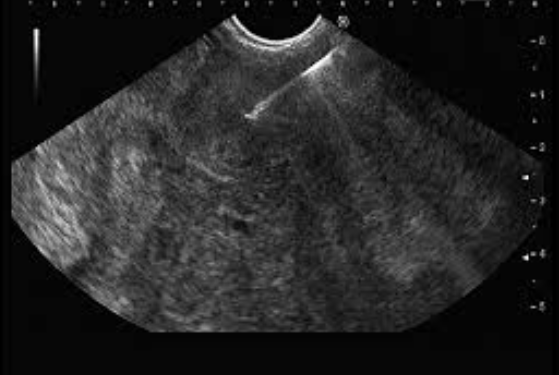

EUS-Guided Tissue Sampling (FNA & FNB)

Fine Needle Aspiration (FNA) and Fine Needle Biopsy (FNB) are techniques performed under EUS guidance to obtain tissue samples from deep-seated structures.

These methods provide accurate diagnosis with minimal risk and avoid the need for more invasive surgical biopsies.